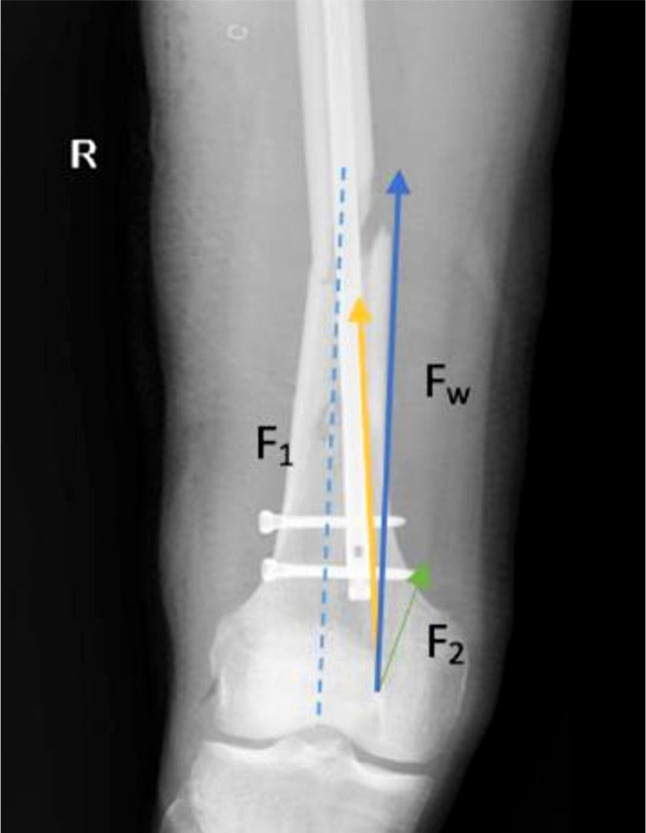

Objectives: In this study, we aimed to investigate whether there was a relationship between deformity at the fracture line/eccentric placement of the nail, and union time (UT) in isthmal diaphyseal femoral fractures treated with intramedullary nails.

Patients and methods: Between September 2017 and December 2020, a total of 61 patients (38 males, 23 females; median age: 47 years; range, 23 to 62 years) with closed femoral shaft fractures who underwent antegrade nailing were retrospectively analyzed. The following parameters were examined: (i) amount of angulation in the fracture line (AFL), (ii) varus/valgus of the fracture line (VAFL), (iii) amount of deviation of the distal tip of the nail from the femoral notch (DDT), (iv) medial lateral orientation of the distal nail relative to the notch (MLON), (v) number of fracture parts (NFP), and (vi) UT.

Results: The causes of injury were high-velocity traffic accidents in 42 patients and falls in 19 patients. The median surgical delay was 4.5 (range, 2 to 8 days). The median follow-up time was 37 (range, 12 to 57) months. There was a moderate, statistically significant and positive correlation between UT and AFL, DDT, and NFP (r=0.486, p<0.001). The difference in UT according to MLON (p=0.002) was statistically significant.

Conclusion: Our study results suggest that impaired weight-bearing force and translational force may cause impaired healing. Thus, angulation of the fracture line and eccentric nail placement may delay fracture union. We recommend using bold screws to ensure that there is no deformity in the fracture line and to fully center the nail inside the distal bone.